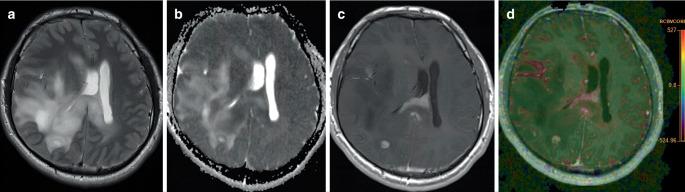

Adult-type and Pediatric-type Diffuse Gliomas : What the Neuroradiologist Should Know.

The classification of diffuse gliomas into the adult type and the pediatric type is the new basis for the diagnosis and clinical evaluation. The knowledge for the neuroradiologist should not remain limited to radiological aspects but should be based additionally on the current edition of the World Health Organization (WHO) classification of tumors of the central nervous system (CNS). This classification defines the 11 entities of diffuse gliomas, which are included in the 3 large groups of adult-type diffuse gliomas, pediatric-type diffuse low-grade gliomas, and pediatric-type diffuse high-grade gliomas. This article provides a detailed overview of important molecular, morphological, and clinical aspects for all 11 entities, such as typical genetic alterations, age distribution, variability of the tumor localization, variability of histopathological and radiological findings within each entity, as well as currently available statistical information on prognosis and outcome. Important differential diagnoses are also discussed.